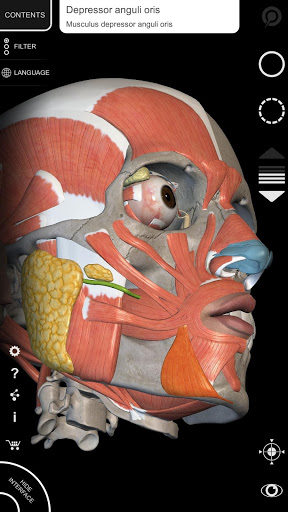

"Anatomía - Atlas 3D" permite estudiar la anatomía humana de forma fácil e interactiva.

A través de una interfaz sencilla e intuitiva es posible observar cada estructura anatómica desde cualquier ángulo.

Los modelos anatómicos 3D son especialmente detallados y con texturas de hasta una resolución de 4k.

La subdivisión por regiones y las vistas predefinidas facilitan la observación y el estudio de partes individuales o grupos de sistemas y las relaciones entre los diferentes órganos.

MODELOS ANATÓMICOS 3D

• Sistema musculoesquelético